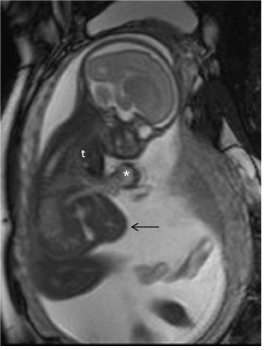

Figure 2: Fetal MRI using single shot turbo spin echo, shows the heart in an ectopic position (*) and eventration of a part of the liver at the midline (arrow). Notice the small thoracic cavity (t). No malformation of the central nervous system could be seen.